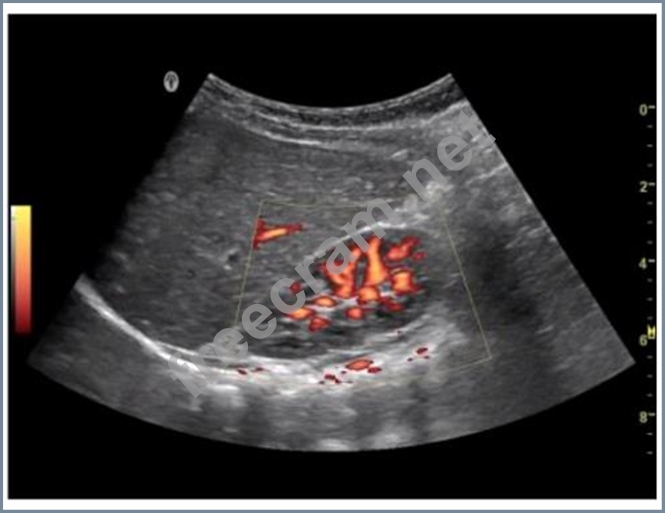

What does this image demonstrate?

Question 28: What does this image demonstrate? (Exhibit)...